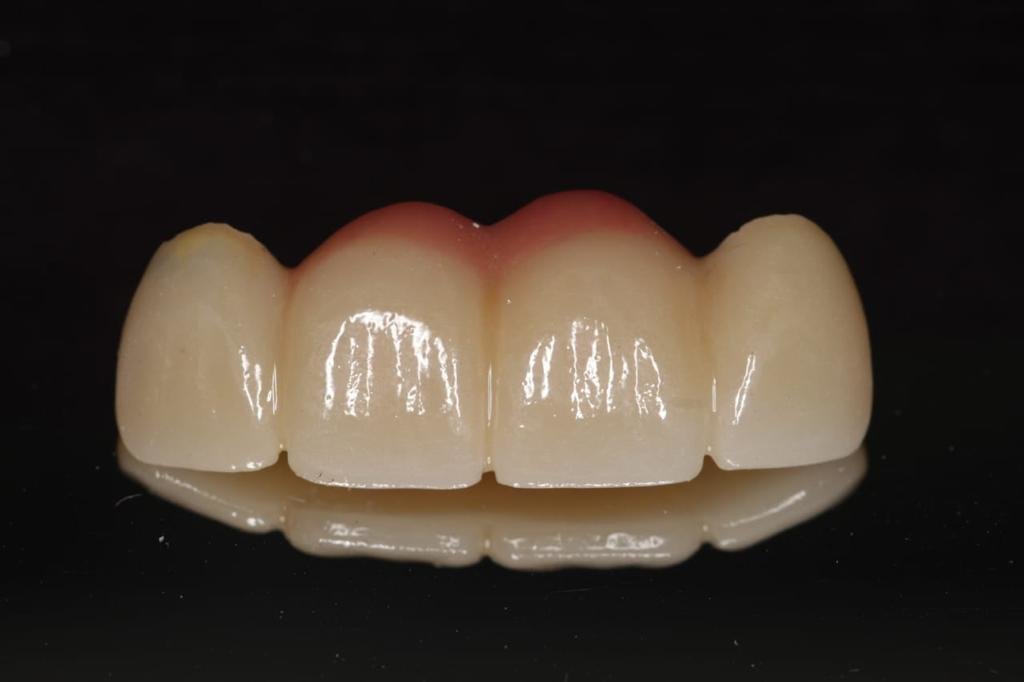

About Live Implants Nicaragua Virgil Mongalo DMD is a dental implant surgeon, past professor of implant surgeries at the University of Miami and the University of Florida has opened a surgical implant center in Managua. This is a state of the art facility consisting of equipped with Ct-scan, 3D Printer, zirconia milling machine, 8 surgical rooms, and USA sterilization controls. His team consists of implant surgeries professor accredited... (Show more)